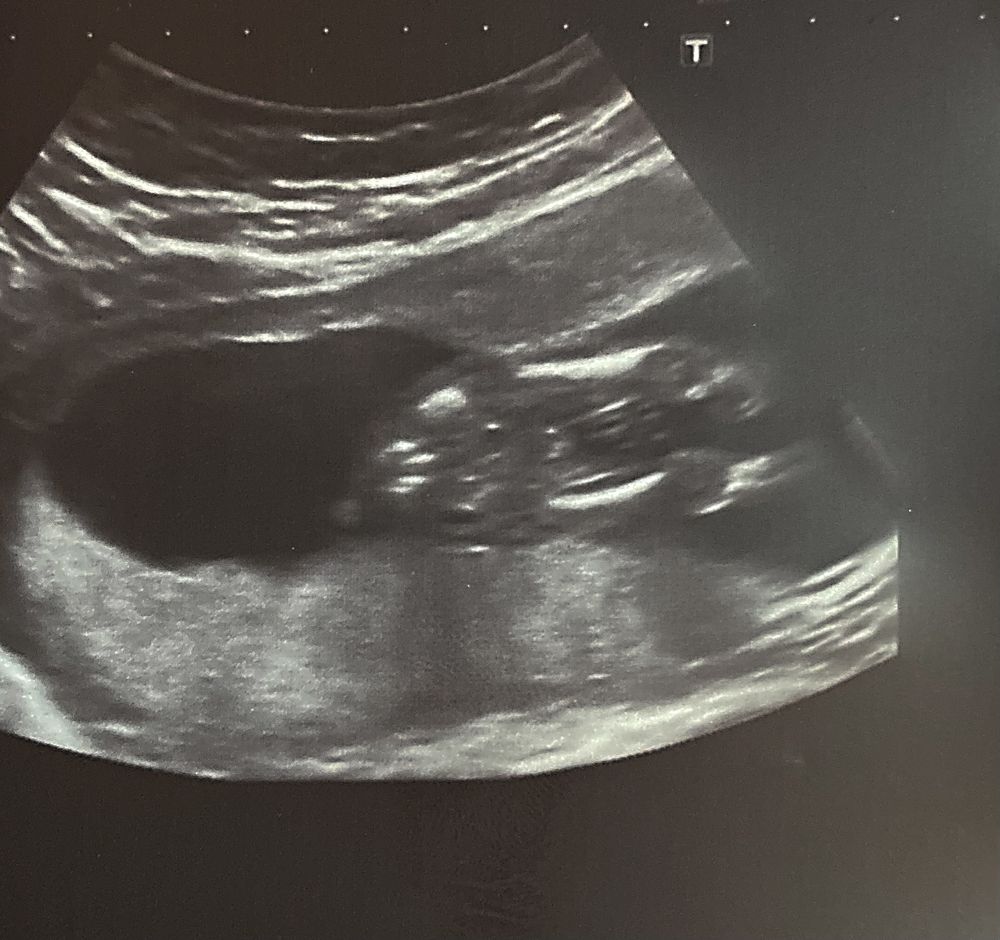

Хотя, конечно, я знаю, что на УЗИ далеко не всегда точно говорят такую информацию и ошибаются, но хочется верить, что предположение верное и второй скрининг это подтвердит ))

с УЗИ у меня есть фото попки малыша, опытные девочки, кто разбирается, посмотрите пожалуйста, скажите своё мнение, потому что я как ни рассматривала его до тортика, так ничего и не поняла 😅

В 16 неделек делала тоже узи по определению пола, тоже сыграли гендер пати, узнали, что сынок будет. Вчера был второй скрининг, оказалось живёт во мне доченька, а то, что узист принял за пипирку, была всего лишь пуповина😄